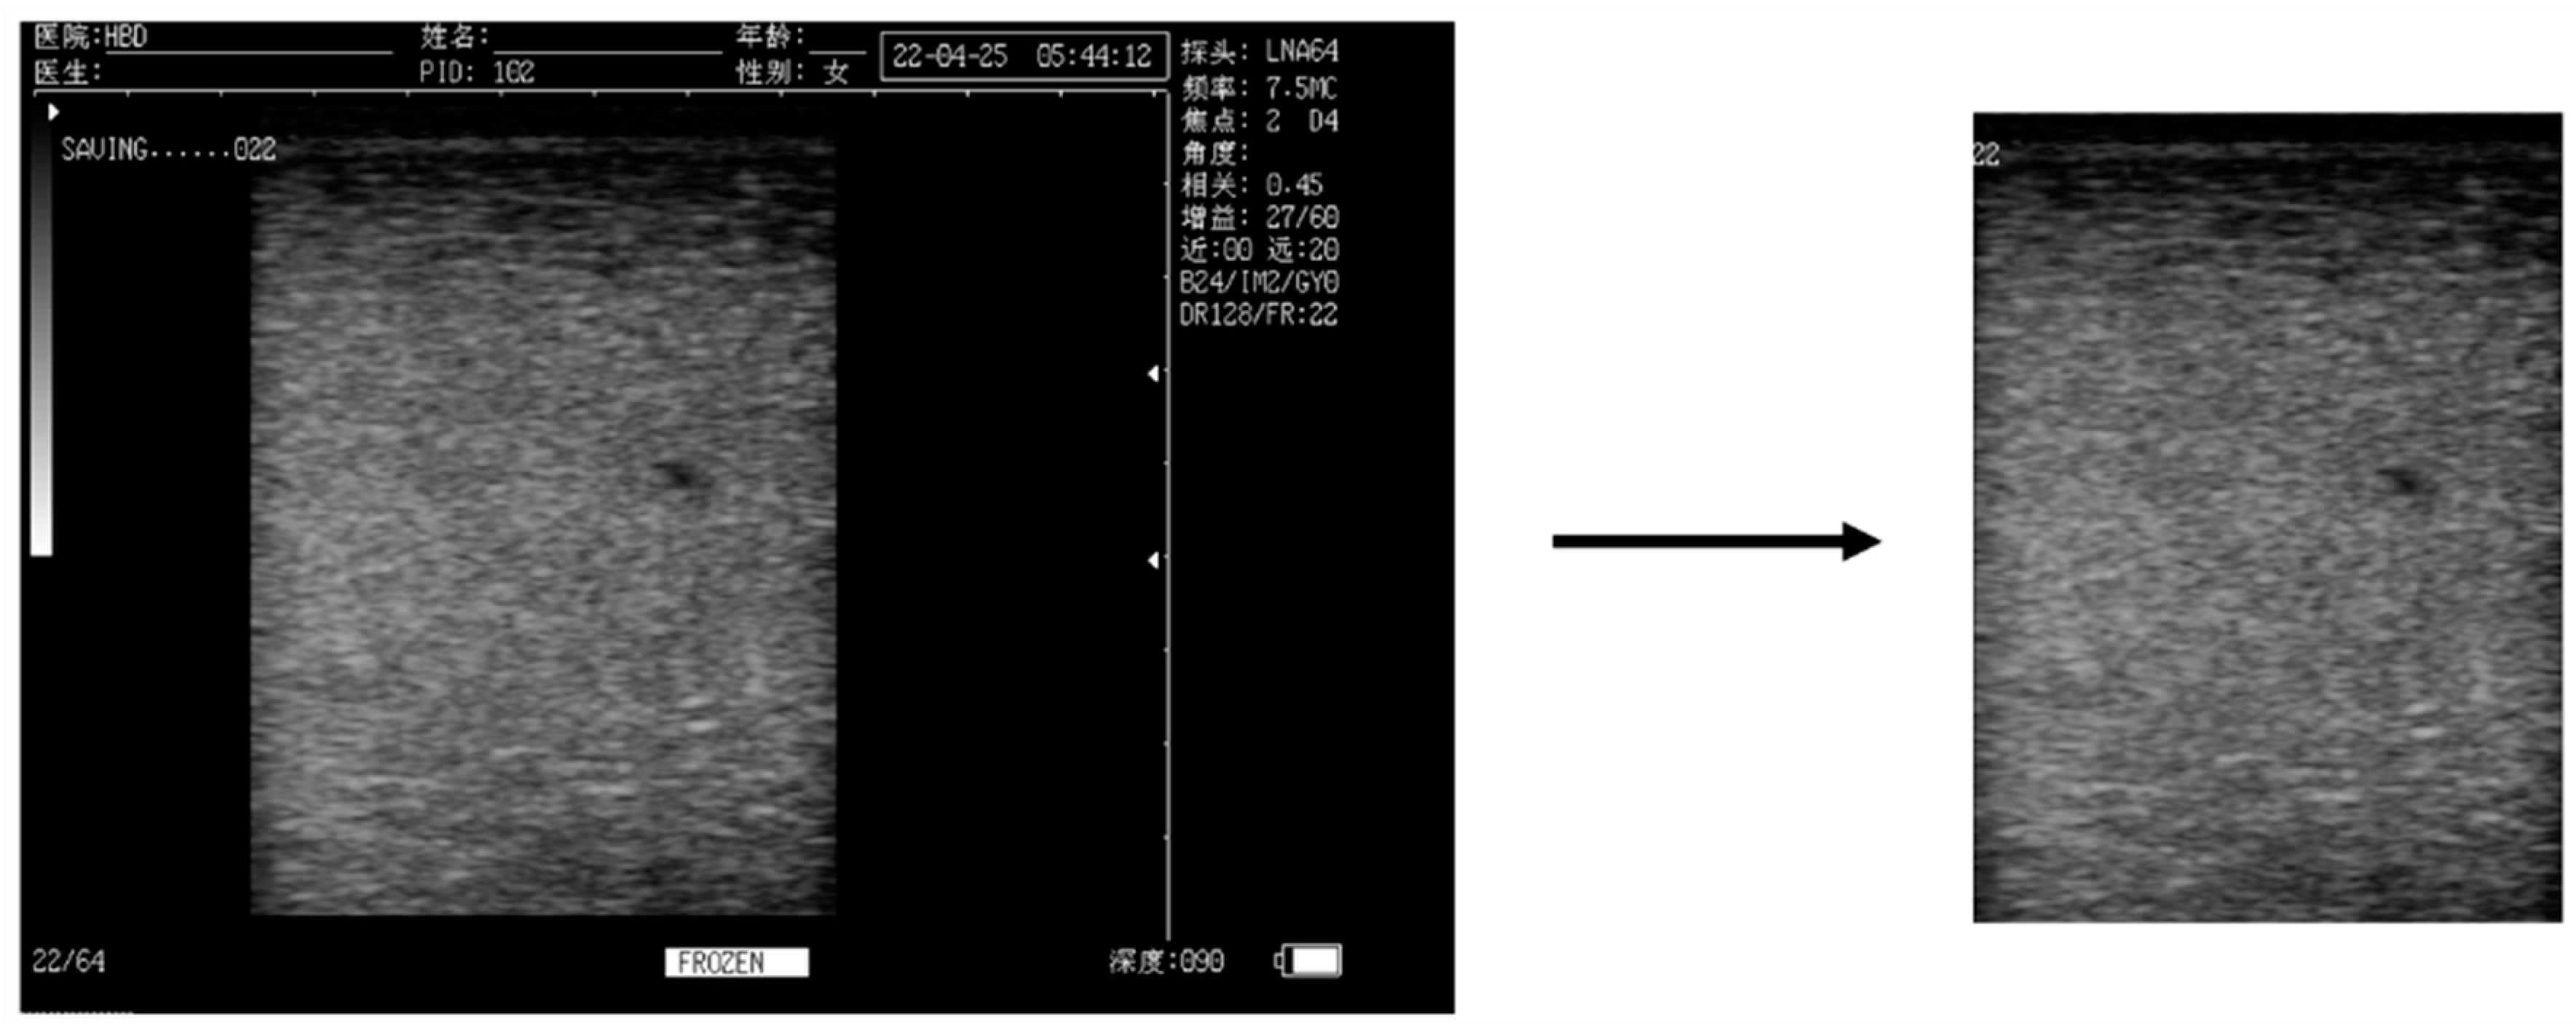

2.1. Data

2.2.1. Data Set Composition